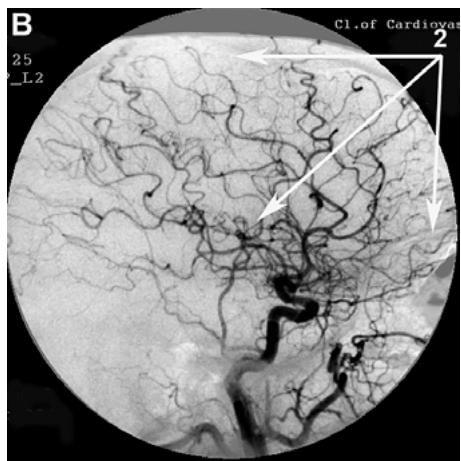

After transcatheter intracerebral laser PBMT, according to digital MUGA, all 48 (100%) patients showed a direct positive result manifested in pronounced angiogenesis, collateral and capillary revascularization, reduction of arteriovenous shunts, as well as an improvement in venous outflow (Figures 1A, 1B, Figures 2A, 2B).

Figure 1: Patient S., 42 years old, male. Medical history of AD - 2 years, TDR-1.

A. Left internal carotid artery angiogram, arterial phase, before transcatheter Intracerebral laser PBMT: 1. hypovascular areas in temporal and frontoparietal regions. B. Left internal carotid artery angiogram, arterial phase, after transcatheter intracerebral laser PBMT: 2. stimulation of angiogenesis, restoration of collateral and capillary blood supply in the temporal and frontoparietal region.